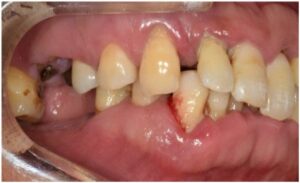

오늘 소개해 드릴

환자분께서는

50대 남성분으로

아래턱 양측 어금니는 상실되었고,

위턱 양측 어금니는 흔들리고 불편하시다며

전체적인 치료를 위해

내원해 주셨는데요.

먼저 구강 내를

확인해 보았더니

만성 치주염으로 인해

잇몸이 부어있고

기구로 건드리기만 해도 피가 날 정도

잇몸 상태가 많이 좋지 않으셨는데요.

정밀한 검사를 위해

파노라마 사진을

촬영해 보았더니

치아를 단단하게 잡고 있어야 할 잇몸뼈가

녹아내려앉아있고,

염증이 있는 치아들도 다수 보였는데요.